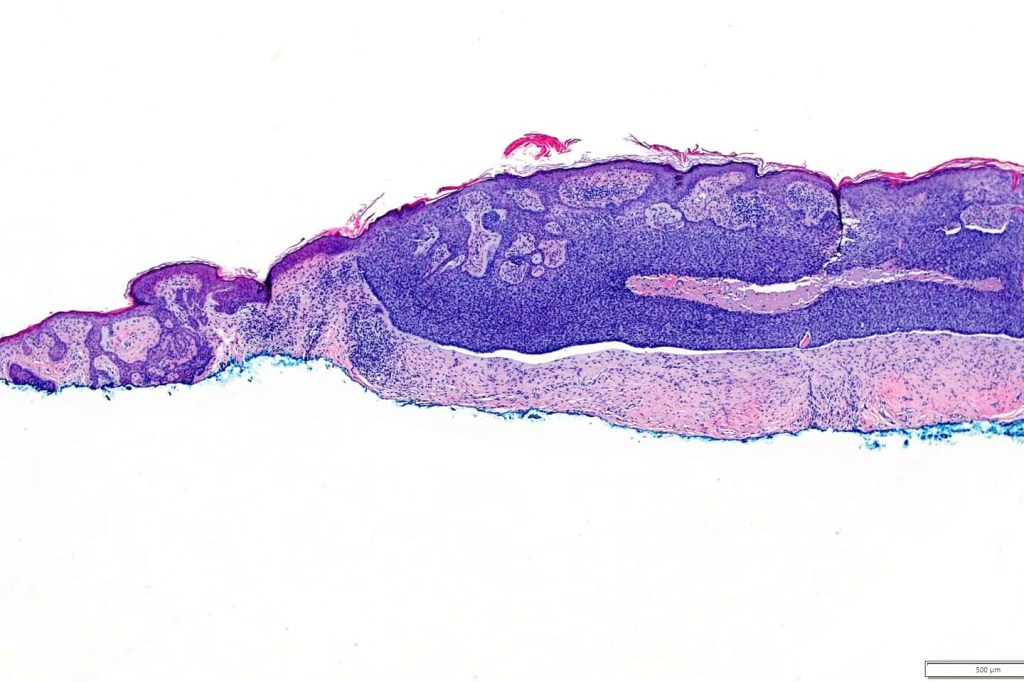

•Vertically orientated, folliculocentric, thin, anastomosing strands composed of basaloid cells embedded in a loose fibrous stroma

•Epidermal origin sometimes evident

•No retraction artifact or stromal mucin deposition